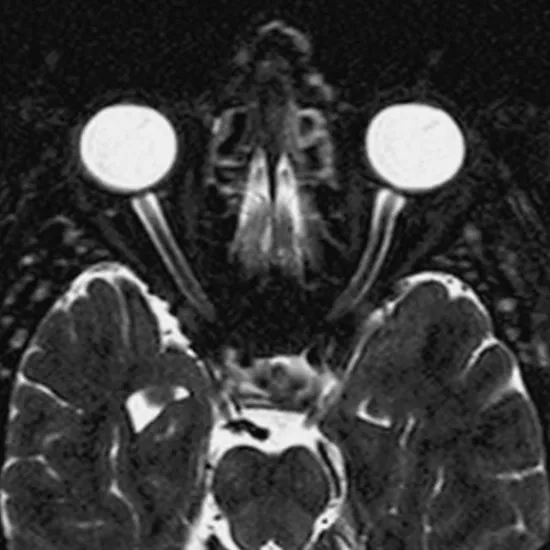

An orbit is a bony cavity that your eye, nerves, muscles, fat, and other soft tissues occupy. MRI scans of the orbits measure the size of masses inside or behind the eye globe. It provides a resolution of soft tissue and explains orbital space for masses.

Orbit MRI scans find tumours, infections, and long-term diseases that affect the structures in and around the orbits. It is also used to find out if someone has Grave's disease.